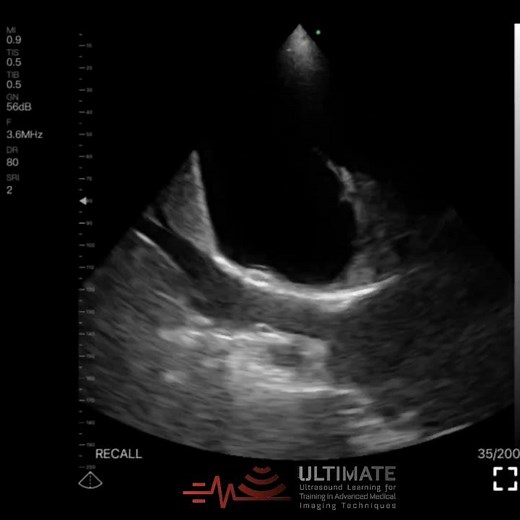

The Flapping Lung Sign, also known as the Jellyfish Sign, is a dynamic sonographic marker of compressive atelectasis in the setting of moderate to large pleural effusion. On B-mode

Radiosign. Tommee Profitt · In The End (Mellen Gi Remix/Slowed Down). The Flapping Lung Sign, also known as the Jellyfish Sign, is a dynamic sonographic marker of compressive atelectasis in the setting of moderate to large pleural effusion. On B-mode ultrasound, the compressed, non-aerated lung appears as a mobile, echogenic, lobulated tissue ...

Lung Ultrasound - Jellyfish Sign

Jellyfish Sign in Lung Ultrasound - ULTİMATE

jellyfish sign . lung ultrasound